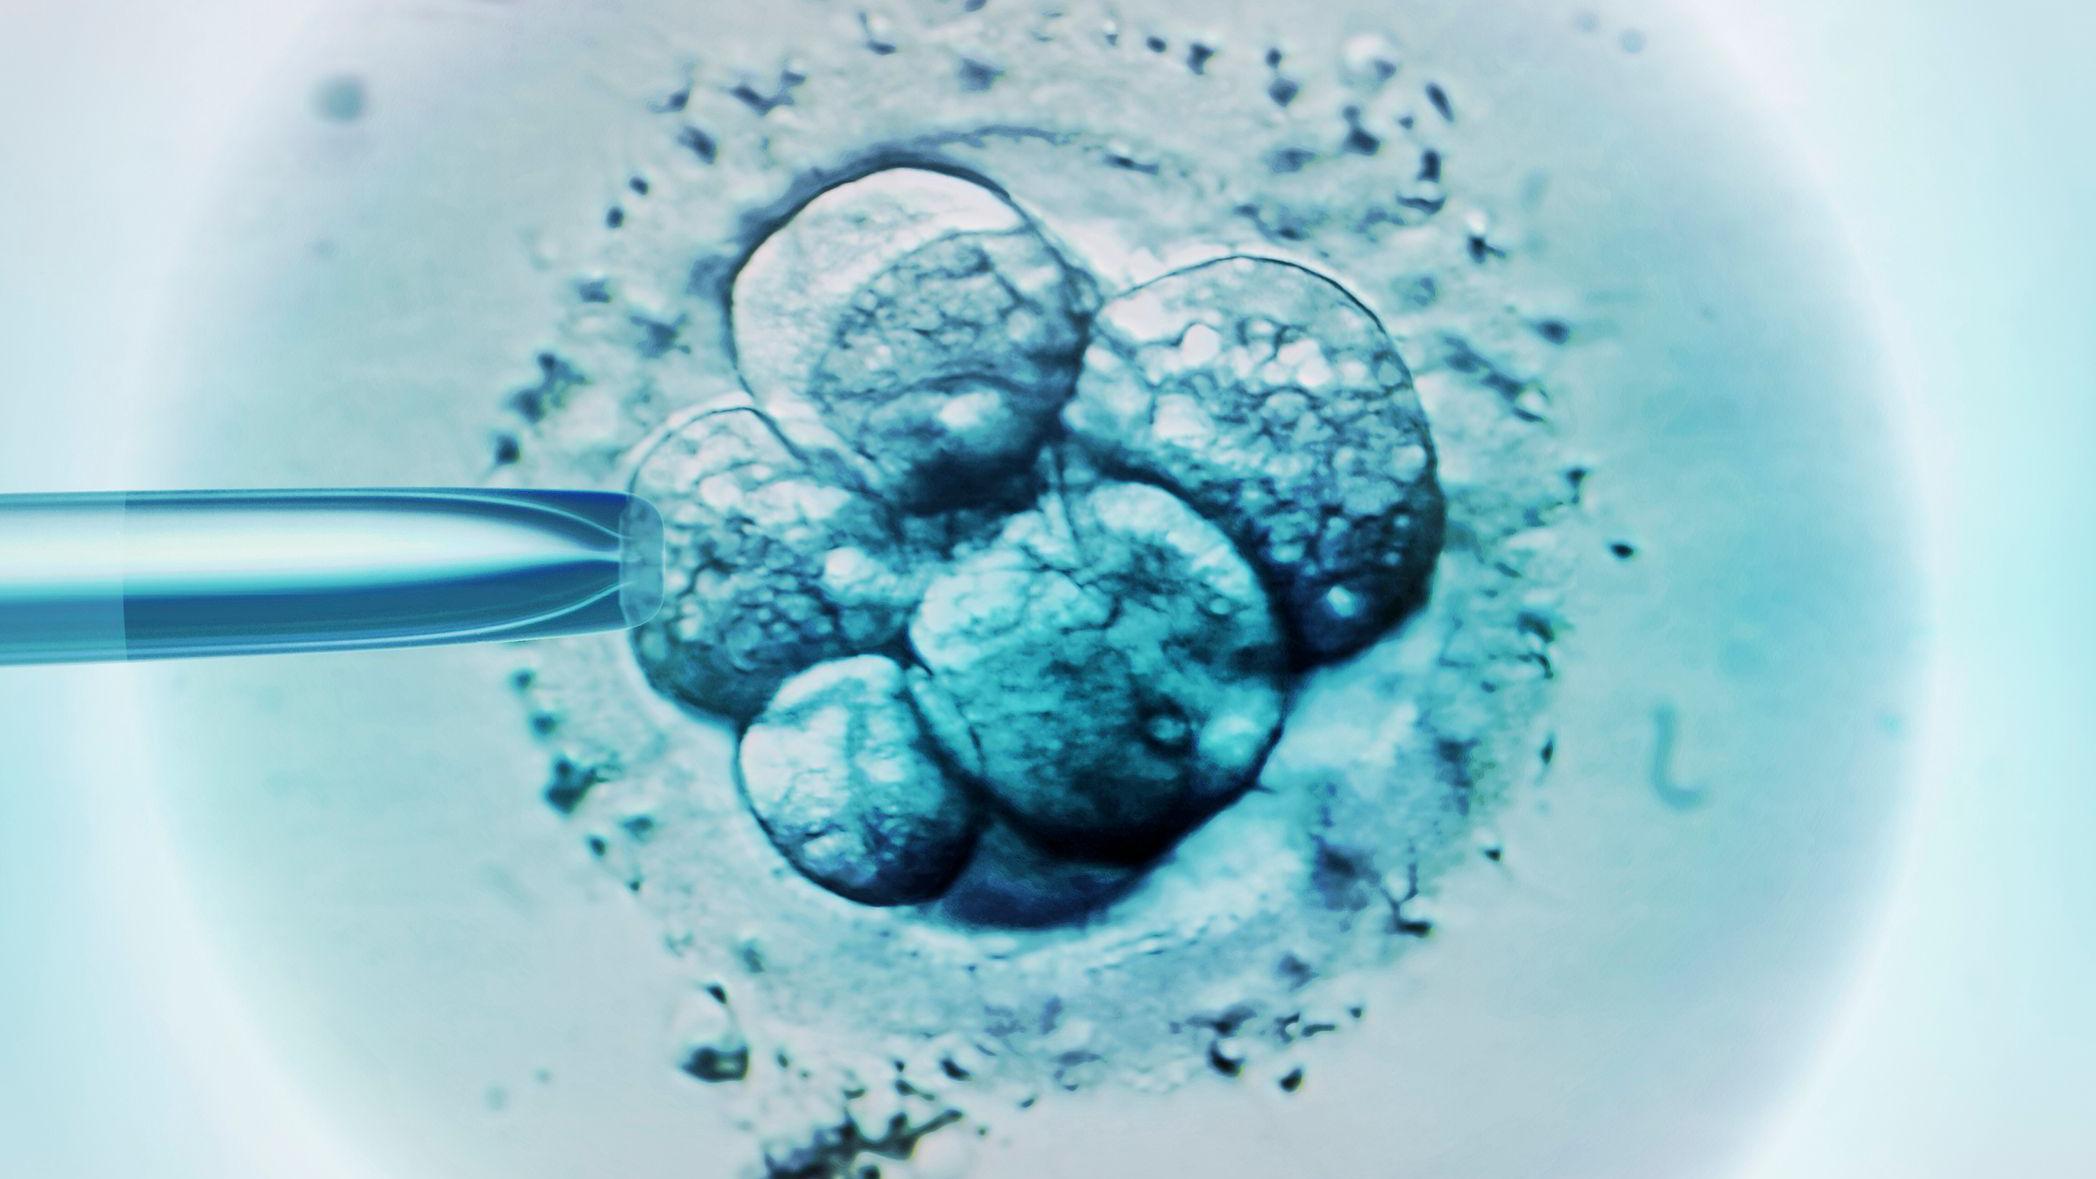

Oplodnja jajne ćelije i majke i donorke vrši se očevom spermom u laboratoriji.

Embrioni se razvijaju dok DNK iz spermatozoida i jajne ćelije ne formira par struktura koji se zovu pronukleusi.